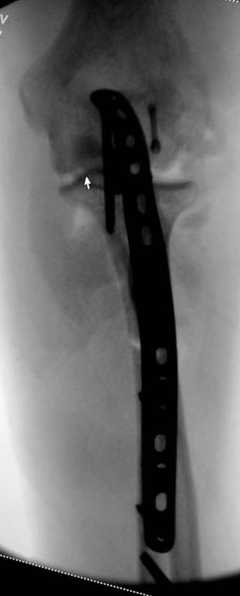

Снимки вот еще какие есть (наши лаборанты пытались сделать что то)

Good day dears colleagues! You presentated only one x-ray proection - lateral- of elbow.Accorden this I thing that this isn't avulsion fracture of olecranon,as usually can to see.This is Monteggia like fracture with subluxation of radial head.If

you can show AP x-ray or more more better CT elbow

I will more sure.Any way more imported of all normal long of ulna.So my recomendation ORIF proximal ulna by LCP - allow normal long by bridging, without attention to continues cortex but attention to articular surfase. On operation examen of radial head,becouse my sence isn't without damage.Operation by standart approach.

Это не перелом локтевого отростка! Безусловно сломан венечный отросток и, может оказаться, что и головка луча. Сложный перелом! Доступ задний, фиксация пластиной (LCP) и стягивающими винтами. Только не по Веберу! Положение больного на животе. ЭОП.

При самом большом к Вам уважении, Сергей Анатольевич, не соглашусь. У меня, после того, как добавили "прямой" снимок, сомнений не осталось. Венечный сломан наверняка. Но чтобы судить, насколько это критично для стабильности, нужно иметь строго боковую проекцию. И при этом помнить, что на него крепятся медиальные связки.

Прикрепляю снимок, где обведен фрагмент, несущий на себе венечный отросток (весь он смещён с этим фрагментом или частично - без качественной боковой проекции судить сложно), и отдельно на снимке обведено "ложе", от которого он сместился.

Здесь выставлены несколько случаев и варианты фиксации локтевого отростка, некоторые в комбинации с другими переломами.

1 вариант применен ACUMED локинг пластина

2 вариант

перелом локтевого отростка с переломом головки лучевой кости (использованы 2 мм шурупы)